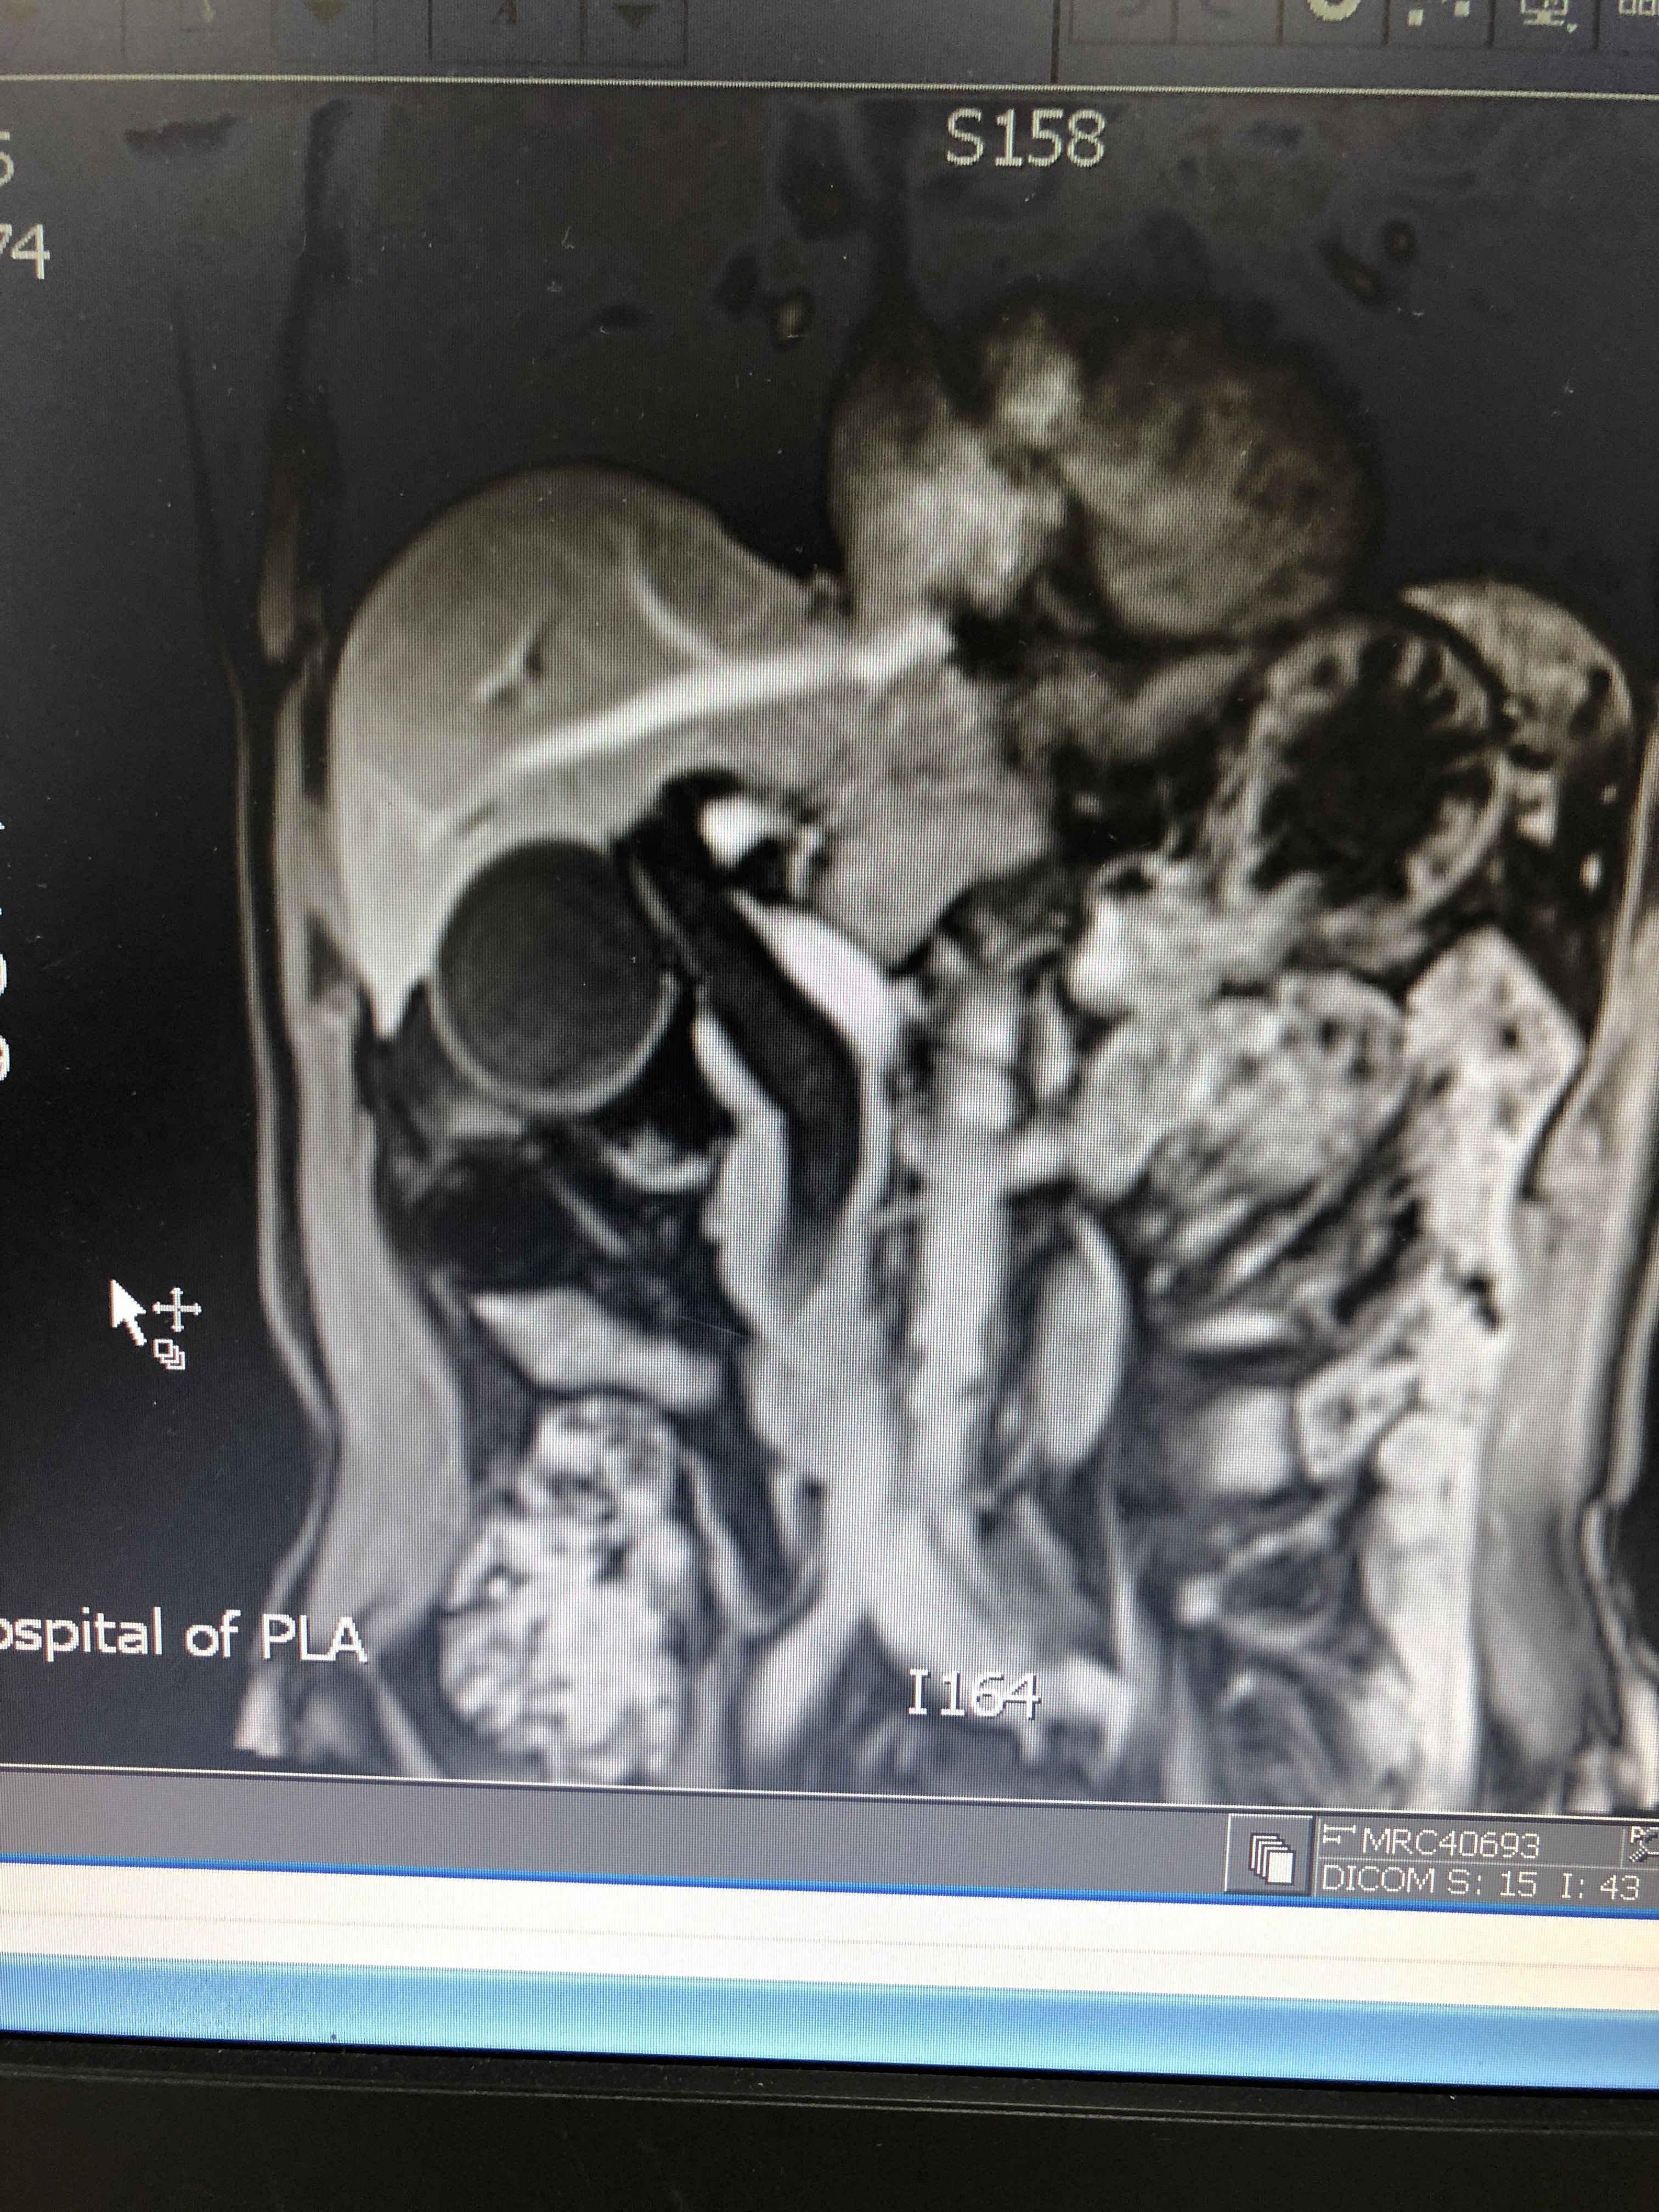

胆管下端狭窄即缩窄性乳头炎伴胆管扩张并

3024x4032 - 2647KB - JPEG